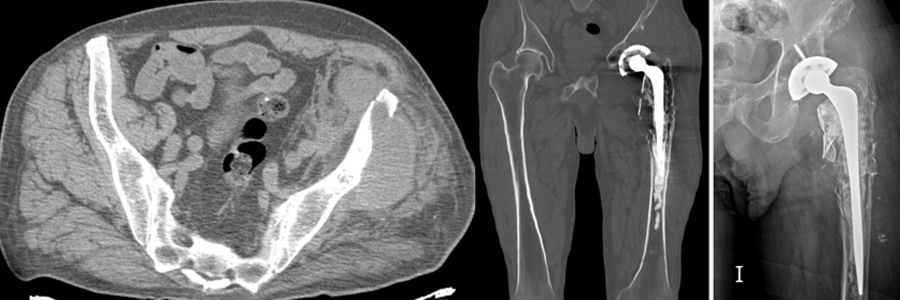

Caso 2 | Abril 2026 | Hospital Italiano Masculino. 73 años. MC: Dolor unilateral en miembro inferior izquierdo de larga evolución (2 meses) que empeora los últimos días.